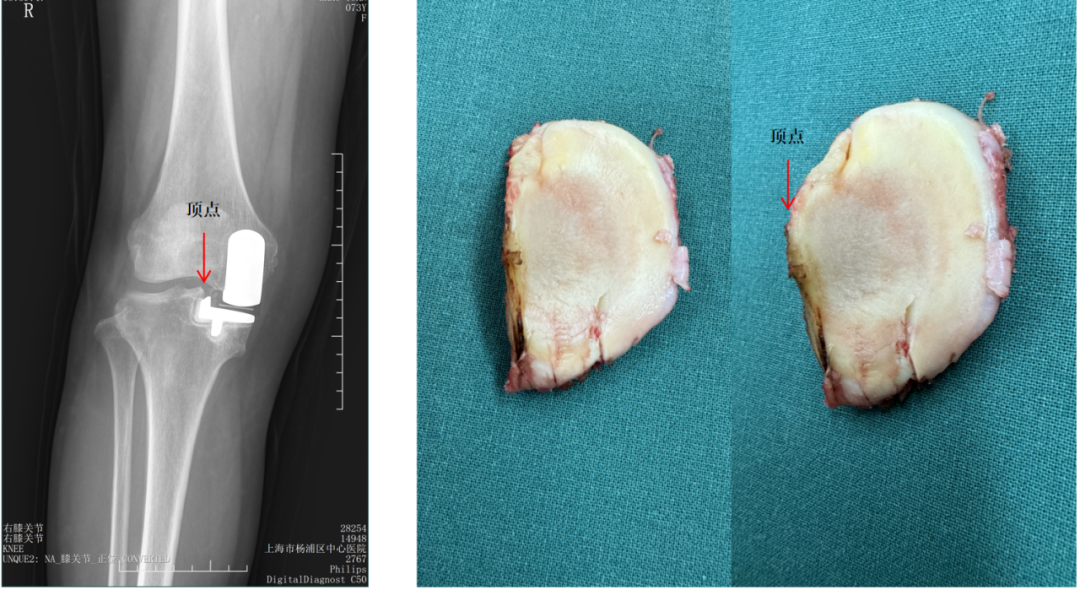

胫骨截骨宽度不足(距离顶点>2mm)

胫骨截骨跨越顶点